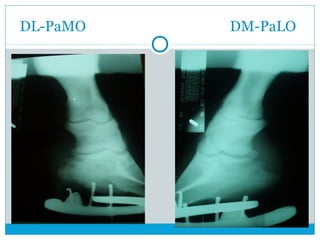

DL-PaMO DM-PaLO

 DorsoLateral Palmaromedial Oblicua

 DorsoMedial Palmarolateral Oblicua